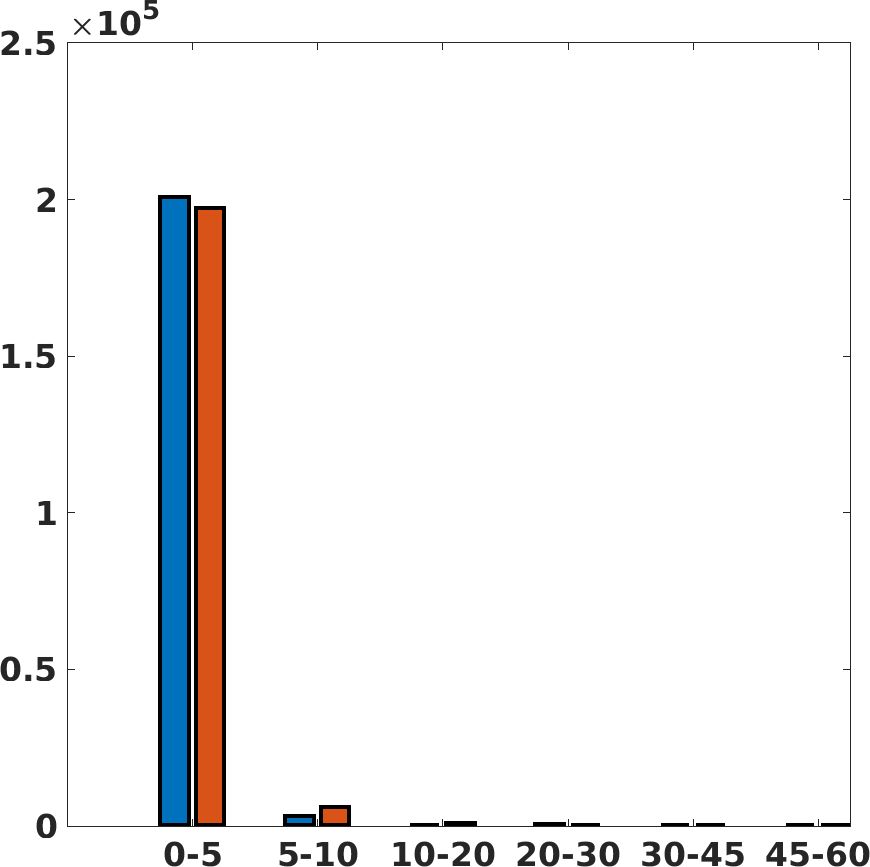

Fig. 17 (left) shows the box plot of the quantitative metrics, comparing the target images with the prediction and the Cubic convolution, respectively. The PSNR metric is computed on a data set of 200 images, belonging to the same district, and with the same up-sampling factor. Analysing the obstetric anatomical district and concerning the corresponding raw images (Fig. 7 (a, left)), the denoising allows the network to significantly improve the results of the up-sampling and the prediction. In particular, comparing the target images with the predicted images, the median PSNR value of obstetric 2X denoised images is 51.8, compared to the median PSNR value of obstetric 2X raw images which is 36.9.

Fig. 17 (right) shows the histogram of the absolute value of the error with respect to the target, of the prediction and Cubic convolution respectively. This result shows that our framework increase of and (2X and 4X, respectively) the number of pixels where the prediction error is lower than 5, which is very similar to the target when visually analysing the images, and improved with respect to the learning framework applied to raw images. According to Fig. 18, our method improves the accuracy of Cubic convolution. For example, the SSIM increases of on cardiac 2X and the MAE increases of on abdominal 4X.